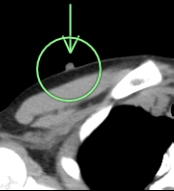

(検診例3)

左肺の下方に1cm大の白い結節(○枠+矢印)が指摘されました。

左乳頭に金属のマーカーをつけて(○枠+矢印)、再撮影しました。結節影と一致しましたので、乳頭であることが確定しました。